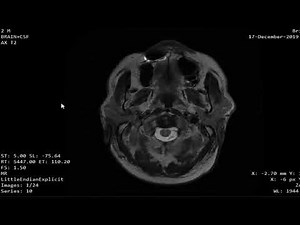

- Brain MRI

Results - Cerebral

Atrophy - MRI On

Head - MRI Brain

Scan Abnormalities - Brain Atrophy